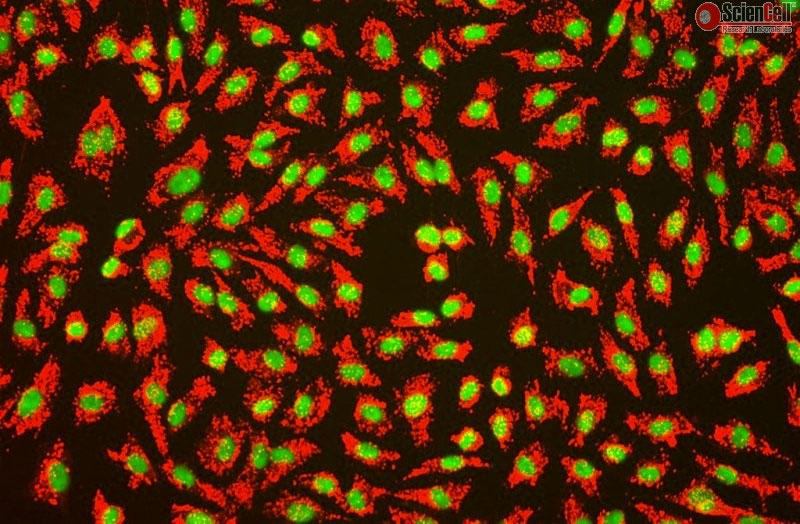

ScienCell社では、HUVEC(ヒト臍帯静脈内皮細胞)を販売しております。

HUVECは、循環器領域における医薬品開発、高分子輸送、血管形成および血管新生の研究などの実験に使用されています。